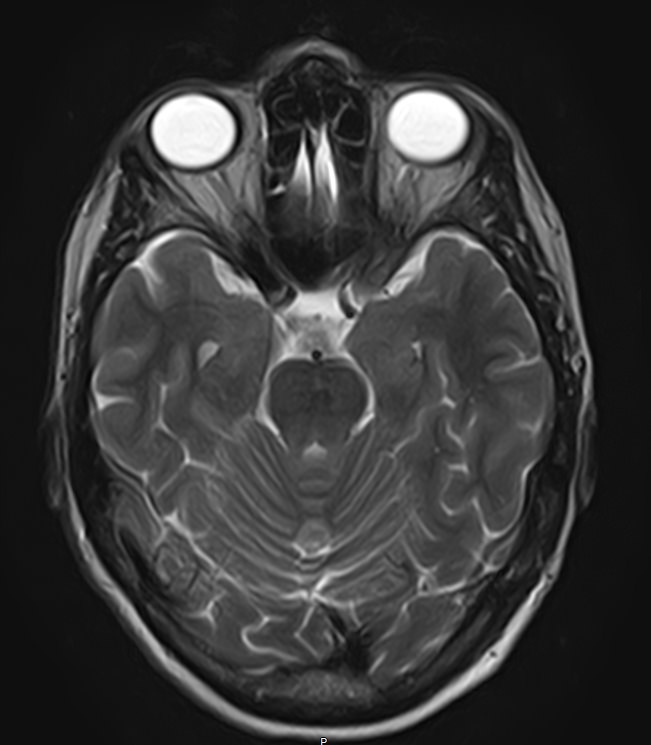

МРТ головного мозга является высокоинформативным методом исследования центральной нервной системы, который дает возможность оценить состояние всех структур головного мозга и поставить правильный диагноз. Стандартную МРТ головного мозга дополняет МР-венография, которая позволяет получить детальную картину строения и функционального состояния венозной системы мозга.

В клинике «Доступная медицина» проводится МРТ головного мозга и МР-венография головного мозга на современном аппарате TOSHIBA VANTAGE TITAN 1,5 Тесла, который обладает высокой чувствительностью и соответствует всем мировым стандартам качества диагностики. Напряженность магнитного поля 1,5 Тесла обеспечивает высокую четкость изображения и позволяет выявлять заболевания на ранних стадиях развития. Процедура МРТ безопасна, так как томограф не испускает рентгеновского излучения, полностью безболезненна и имеет доступную стоимость.

• очаги ишемического и геморрагического инсульта, область поражения, признаки отека головного мозга, стадию развития заболевания;

• характерные признаки дегенеративных заболеваний головного мозга (болезнь Альцгеймера, старческая деменция, болезнь Паркинсона), определить изменения коры головного мозга и подкорковых структур;

• поражение структур головного мозга на фоне травм, гематомы головного мозга;